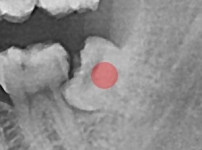

部分埋伏智齿